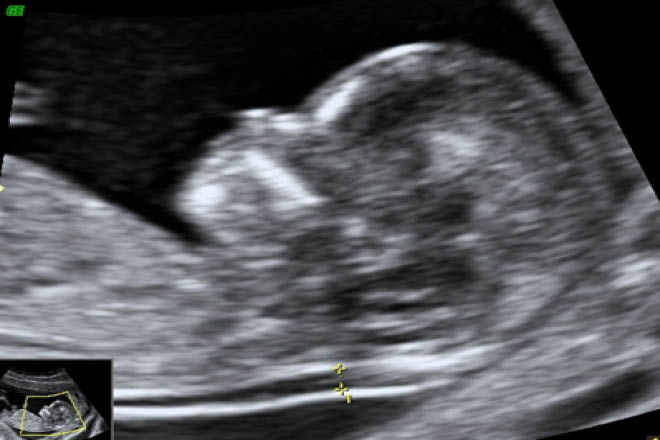

- Ecografia de caderas pediatrico